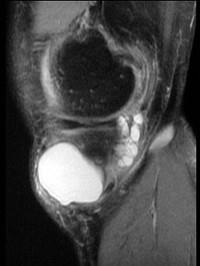

问题 男,21岁,膝关节疼痛,行走困难,曾有外伤史,请结合所提供的图像,选择最佳选项 ( )

选项 A、未见异常 B、前十字韧带撕裂与巨大半月板囊肿 C、内侧半月板撕裂 D、巨大半月板囊肿 E、内侧半月板撕裂与巨大半月板囊肿

答案 E